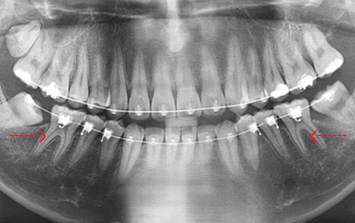

아래쪽 사랑니 두 개가 심하게 누운 상태로 내원, 오른쪽 사랑니는 인접치아를 누르고 있고 왼쪽 사랑니는 음식물이 잘 끼고 가끔 염증이 생긴다고 합니다.